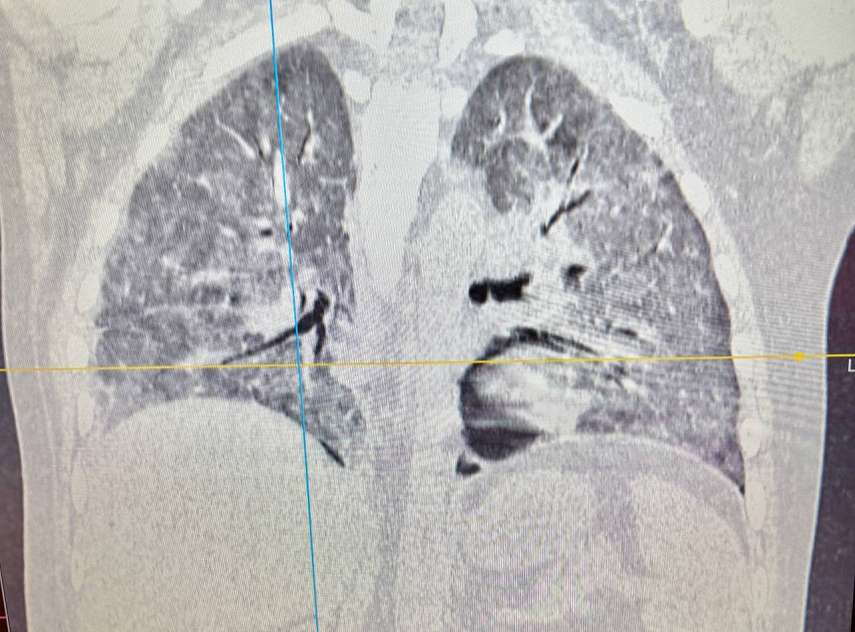

Оказалось, что у кузбассовца тяжелая пневмония, его положили в больницу. Также пересаженная печень стала функционировать с нарушениями.

Медики провели гемодиафильтрацию и обширную антибиотикотерапию. Пациента постепенно перевели с искусственной вентиляции легких на самостоятельное дыхание. В результате жизнь молодого человека удалось спасти.